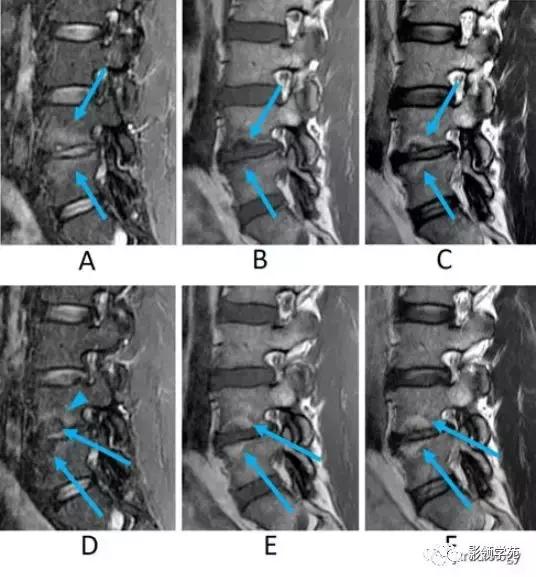

- 1型改变

1、T1WI呈低信号,FS-T2WI或STIR呈高信号(图3-A箭头)。

2、病理提示富血供的纤维组织(图3-A,B,C)。

- 2型改变

1、在T1WI和T2WI上均具有高信号,在FS-T2WI或STIR呈低信号(图3-D箭头)。

2、病理提示脂肪变性(图3-D,E,F)。

- 这些信号变化通常出现在腰椎,特别是L4/5和L5/S1的水平。

- 有时在临床病例中这些终板改变类型常常共存(图3)。

图3:椎间骨软骨病的典型病例(Modic 1型和2型)。男,50岁。

A:STIR矢状位图像,

B:T1WI矢状位图像,

C:T2WI矢状位图像,

D:STIR矢状位图像,

E:T1WI矢状位图像,

F:T2WI矢状位图像。

A-C:初次检查。D-F:18个月后复查。

最初的检查(A-C)STIR上示终板的高信号并椎间隙变窄(A箭)。该区域在T1WI上呈低信号(B箭),在T2WI上呈高信号(C箭),表明Modic 1型终板变化。

18个月后复查(D-F),发现骨髓脂肪变性,表明转变为Modic 2型改变(D,E,F箭)。部分保留的骨髓水肿在 STIR上呈高信号(D箭头)。